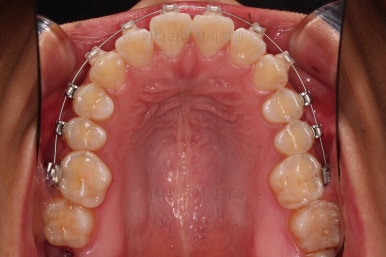

1. 초진 시 입안의 모습 평가

부산연산역치아교정 키다리아저씨치과에 처음 내원했을 당시의 입안의 모습이비다.

앞니 약간, 어금니쪽 약간 삐뚤어진 것, 그리고 위아래 앞니가 약간 뻗쳐 보이는 양상 이외에는 매우 가지런해 보여서 교정치료를 굳이 왜 하시려고 하지? 라고 생각될 정도의 치열 상태였습니다.